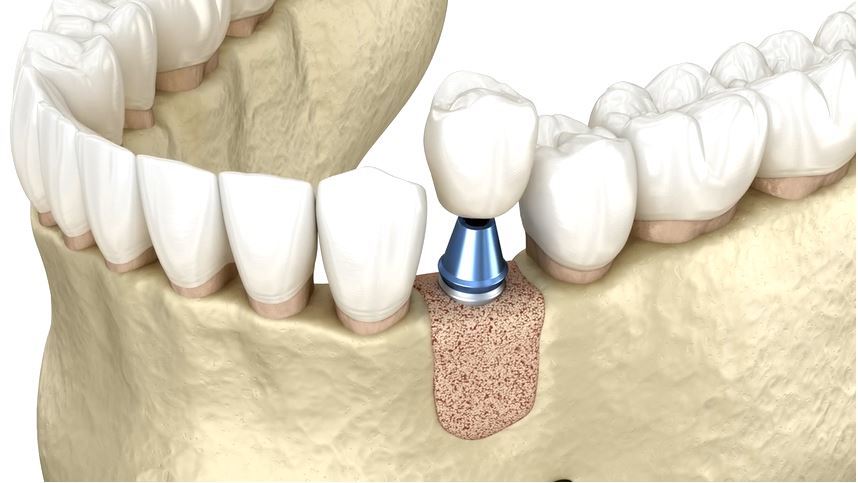

انواع روش های پیوند استخوان و مزایا و معایب هر کدام در کاشت ایمپلنت دندان در ونک. بازسازی استخوان یکی...

عوارض احتمالی و ریسکهای مرتبط با پیوند استخوان در جراحی ایمپلنت در ونک. امروزه کاشت ایمپلنت دندان به...